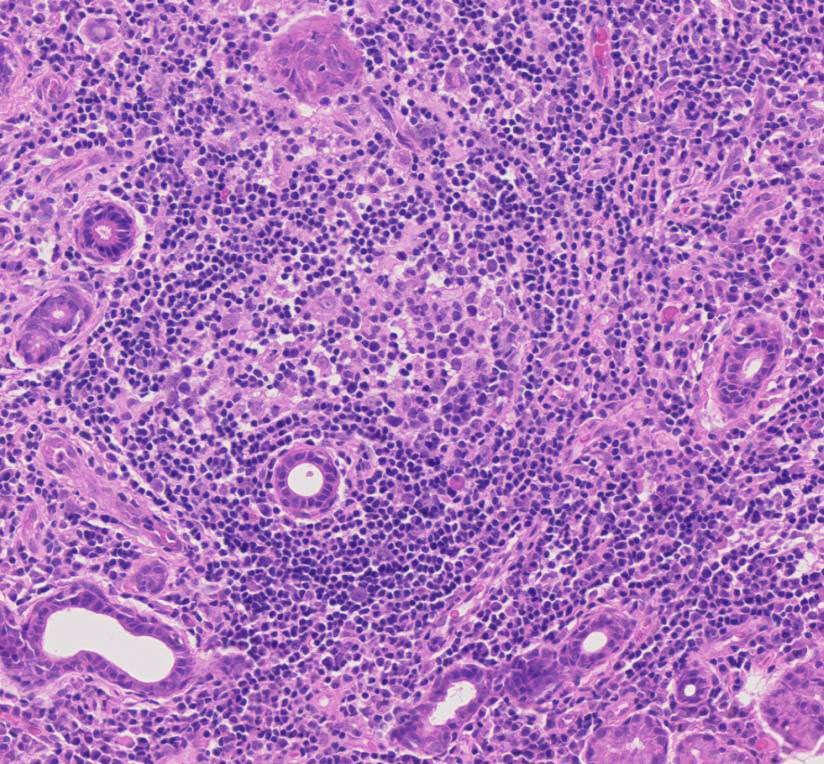

Figure 3

Immunohistochemistry staining for CD20 and CD3 in sequential sections of a labial salivary gland sample showing a large, segregated focus with a predominant B cell infiltrate.

Activated CD4+ T cells predominate in small aggregates and decrease in severe lesions. B cell infiltration predominates in the larger foci (fig. 3) [20, 21]. Accordingly, the T/B cell ratio is negatively associated with the degree of inflammation [20]. On the other hand, the percentage of CD8+ T cells and natural killer (NK) cells does not significantly change with lesion severity [20]. Regulatory T cells (Tregs) are also found in SS lesions and their frequency varies according to lesion severity, with the highest frequency found in intermediate size lesions [21].